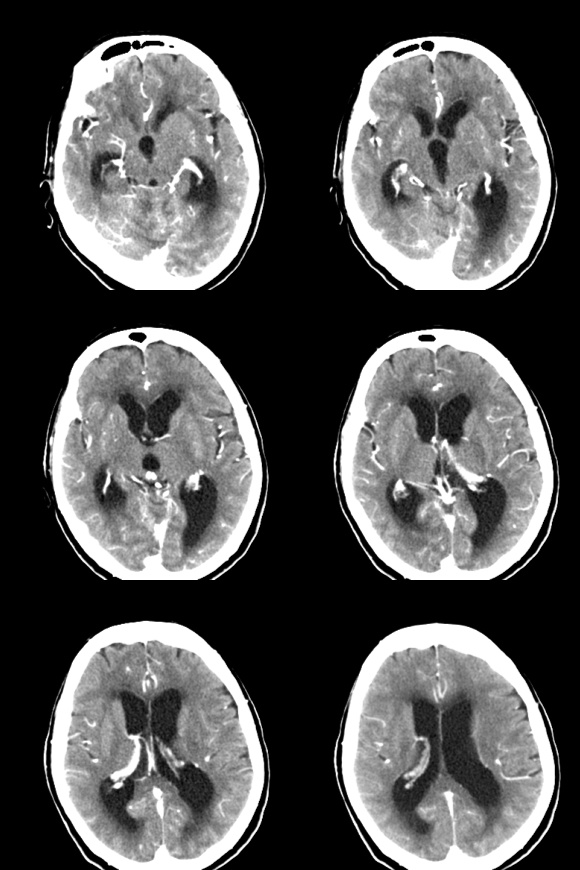

标题: CT18179:F67y,反复头昏、头痛。 [打印本页]

标题: CT18179:F67y,反复头昏、头痛。

67岁女性,头昏、头痛1年+。

小脑蚓部血管母细胞瘤伴脑室扩张积水。

考虑:小脑蚓部血管母细胞瘤伴脑室扩张积水。

支持考虑:小脑蚓部血管母细胞瘤伴梗阻性脑积水。

血管母细胞瘤一般呈囊性,周围无水肿,增强可见壁结节!此瘤这几种征象没有!

考虑星形细胞瘤或室管膜瘤!!

首先考虑小脑蚓部血管母细胞瘤伴梗阻性脑积水。鉴别诊断转移瘤。

该年龄段本部位好发肿瘤有:星形细胞瘤;室管膜瘤;脉络膜肿瘤;血管母细胞瘤;转移瘤;

征象:肿块形态欠规整,境界欠清,可见实性和囊性两部分,囊性部分增强可见壁有强化;实性部分有囊变坏死,增强强化明显;

拟诊:室管膜瘤;

血管母细胞瘤:好发于小脑半球,多为大囊小结节型,增强特有的亮灯征不明显,且其壁应该无强化;